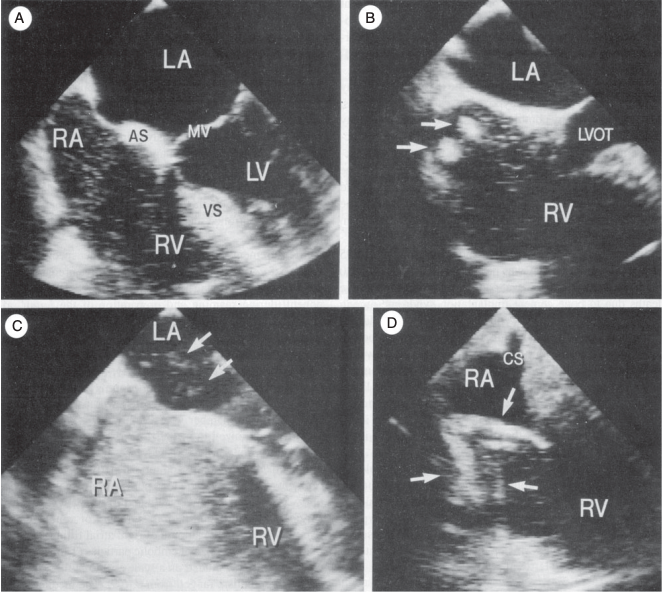

骨水泥反应综合征(Bone Cement Implantation Syndrome,BCIS)首次报道于 1961 年,最常见于髋关节置换术,其特征包括缺氧、肺血管阻力增加、低血...